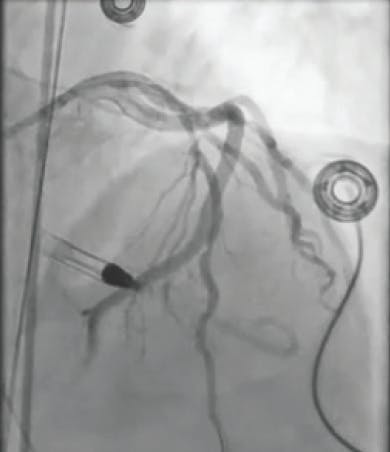

A 2-mm balloon was used to perform the Dotter technique to predilate the vessel (Figure 1). Heavy thrombus burden was visualized angiographically, and it was decided that mechanical thrombectomy with CAT RX would be introduced (Figure 2). After multiple passes of CAT RX with 30 seconds of aspiration each, there was improved flow through the vessel (Figure 3). Then, 4- X 38-mm and 4- X 32-mm drug-eluting stents (DESs) were placed distally and in the midbody, resulting in thrombolysis in myocardial infarction (TIMI) 3 flow (Figure 4).

Figure 1. An angiogram shows an occluded right coronary artery (RCA).

Figure 2. Heavy thrombus burden was visualized angiographically after using the Dotter technique.